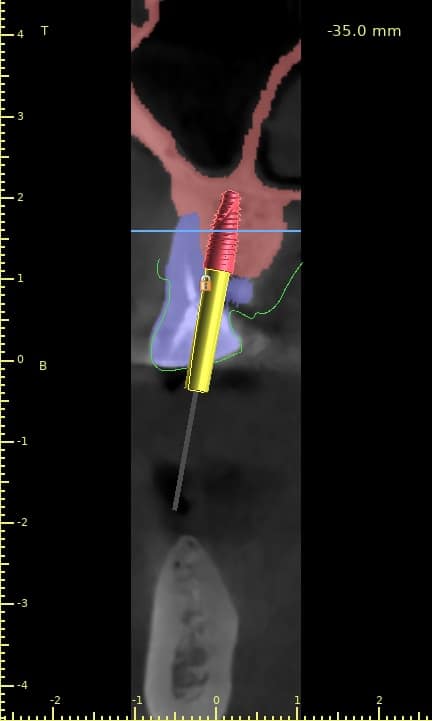

Case of the day where i extracted the 34-35-36 and an immediate placement of 2 implants in the 34-36 sites

sticky bone grafting GTO by osteobiol was used with straumann xenograft